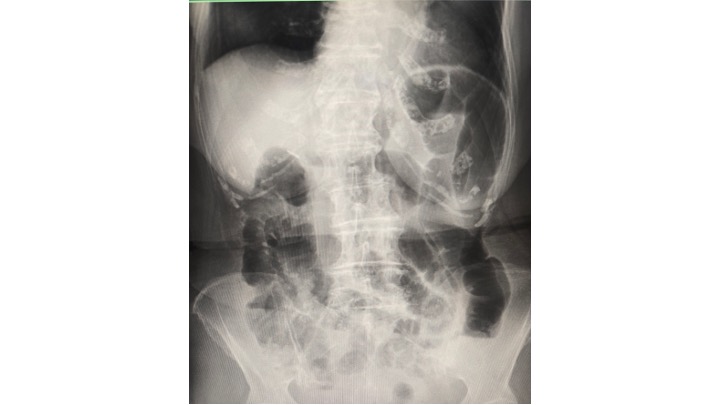

腹部レントゲンを取ると、大腸全体に貯留するガスと、一部小腸ガスを認め、”イレウス(腸閉塞)”と診断しました。

S状結腸ないし下行結腸に赤丸で示す、閉塞機転を認めます。